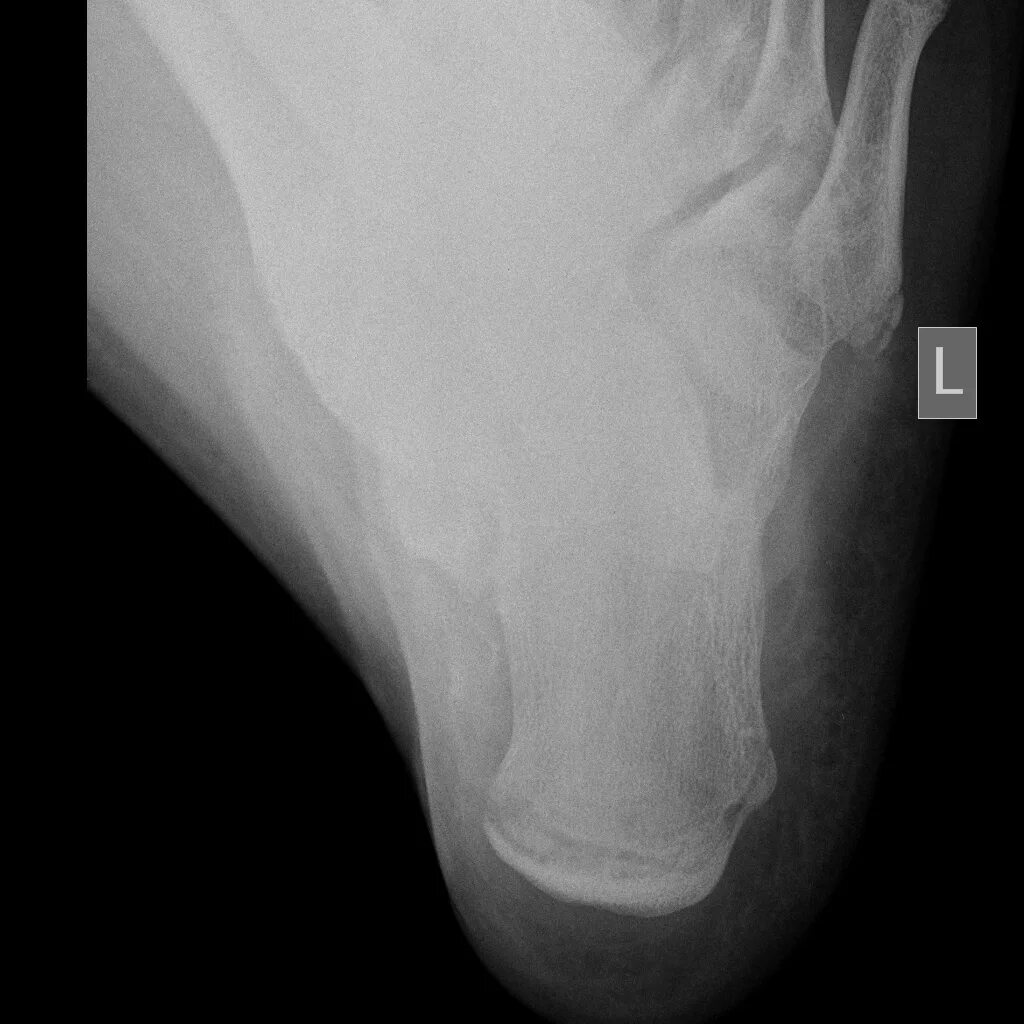

Болезнь шинца у детей код по мкб